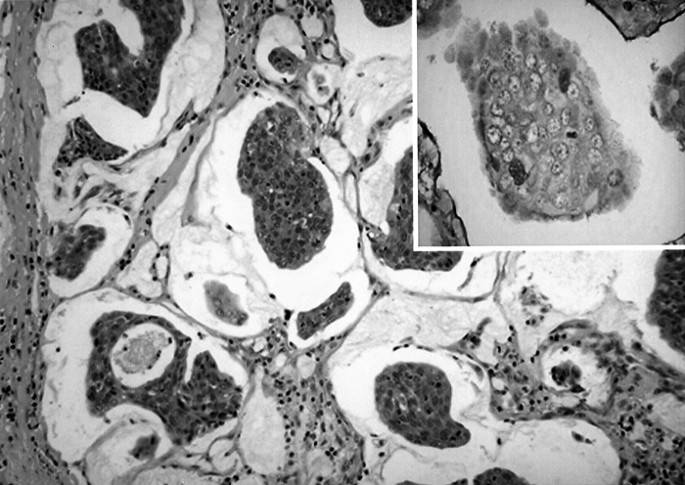

Lacrimal sac carcinomas are believed to arise de novo or, less commonly, from a preceding papilloma.2,4 Squamous and transitional cell carcinomas are the most common, but other types include adenocarcinoma, oncocytic adenocarcinoma, mucoepidermoid, poorly differentiated, and adenoid cystic carcinoma; carcinomas have a quoted recurrence rate of 50% (mortality increasing with recurrence), and 37.5% mortality has been reported after wide surgical excision and radiotherapy.1,3 Squamous cell carcinomas (cases B and F) can exhibit a wide range of differentiation—atypical squamous cells (with abundant eosinophilic cytoplasm, pleomorphic nuclei, prominent nucleoli, and mitotic figures) showing invasion of deeper tissue layers (Figure 1b). Transitional cell carcinoma (cases C and H) resembles that of the urinary bladder, with pleomorphic cells and prominent nucleoli (Figure 2c). Adenoid cystic carcinoma can display a cribriform or basaloid pattern— the former resembling ‘Swiss cheese’, with sharply demarcated aggregates of small tightly packed malignant cells and rounded cystic foci (case I).14 Mucoepidermoid carcinoma (case E; Figure 4) has both epidermoid and mucous-secreting cells with mucin-filled cystic spaces, while oncocytic adenocarcinoma shows oncocytic cells with nuclear atypia, arranged in an infiltrative pseudoglandular pattern.15,16

Nonepithelial lacrimal sac tumours include mesenchymal lesions, lymphoid lesions, malignant melanoma, and granulocytic sarcoma.7 Fibrous histiocytomas, showing a mixture of spindle-shaped fibroblastic cells and plump histiocyte-like cells, are the commonest of mesenchymal tumours and usually benign.17 Haemangiopericytoma (case G) has metastatic potential, and typically demonstrates a vascular pattern of sinusoidal spaces, between which are spindle-shaped pericytes.18 A spectrum of lymphoid lesions of the lacrimal sac may occur, from atypical lymphoid hyperplasia to non-Hodgkins B-cell lymphomas.10,11 Lymphoma (Figure 3) occurred in five cases (33%) of the present series, this being a higher proportion than the 8% reported in a previous series of 117 patients.7 Malignant melanoma, granulocytic sarcoma, lipoma, and neurofibroma are all very rare nonepithelial lacrimal sac tumours and not observed in our series. Recurrence and mortality rates for nonepithelial tumours vary: benign fibrous histiocytoma has a good prognosis if completely excised, while the malignant potential of haemangiopericytoma can be unpredictable.2,18 Lymphomas respond to radiotherapy and chemotherapy, with outcome depending on the extent and type of tumour, whereas malignant melanoma carries a bad prognosis, which is little altered despite aggressive treatment.10,12,13 Encouragingly, all of the nonepithelial tumours in the present series (five lymphomas and one haemangiopericytoma; follow-up from 16 months to 9 years) had a favourable prognosis.